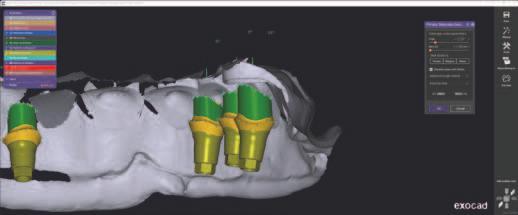

Instrumentele d g tale de astăz pentru stomatolog e pot f ut l zate de la etapa de plan f care până la restaurăr le f nale. După cum demonstrează acest art col, plan f carea tratamentulu poate f real zată în mod d g tal pentru ef c ență ș rezultate îmbunătăț te. Procesul complet al protezelor în cazul prezentat a var at de la ut l zarea punctelor de refer nță sol de ex stente pr n ntermed ul m n - mplantur lor ex stente,

fotograf a b d mens onală (2D), plan f carea d g tală a mplantur lor, scanarea ntraorală, până la o metodă de mpr mare în 3 d mens un (3D) pentru fabr carea unu protot p de reab l tare fullmouth. Această abordare a perm s stab l rea une d mens un vert cale corecte a ocluz e ș a une estet c bune. S-au folos t mater ale progres ve precum z rcon a monol t că ntegrală cu contur total pentru a obț ne estet ca ș un rezultat durab l.

Supraprotezele ex stente poz ț onate în relaț a ocluzală curentă a pac ente ș apo crestele edentate au fost d g tal zate (f g. 4). Zona de proecț e pe modelele dentare analogce a fost decupată pentru a ajuta la montarea d g tală încruc șată. Acest lucru perm te capturarea nformaț -

lor despre creasta edentată în ceea ce pr vește relaț a ș d mens unea vert cală ș transferul acestor nformaț în so ware-ul de pro ectare as stată de calculator (computer-aded des gn, CAD) (f g. 5). În acest caz, a fost folos t un modul so ware pentru proteze dentare pentru a crea o nouă setare d g tală ce poate f t păr tă în scopur d agnost ce (f g. 6). Atașamentele ex stente ale m n - mplantur lor ar f preluate drect în cab net folos nd mater alul rad opac react v la cald; acest lucru ar perm te o tehn că duală de scanare CBCT pentru a fac l ta setarea d agnost că în plan f carea mplantur lor. Scopul no setăr este de a testa d fer te aranjamente dentare, de a reduce expunerea g ng vală ș de a ver f ca spaț ul restaurator d spon b l pentru a as gura un plan de reab l tare prec s, deoarece acest lucru ar putea afecta poz ț a ș d str buț a mplantur lor.